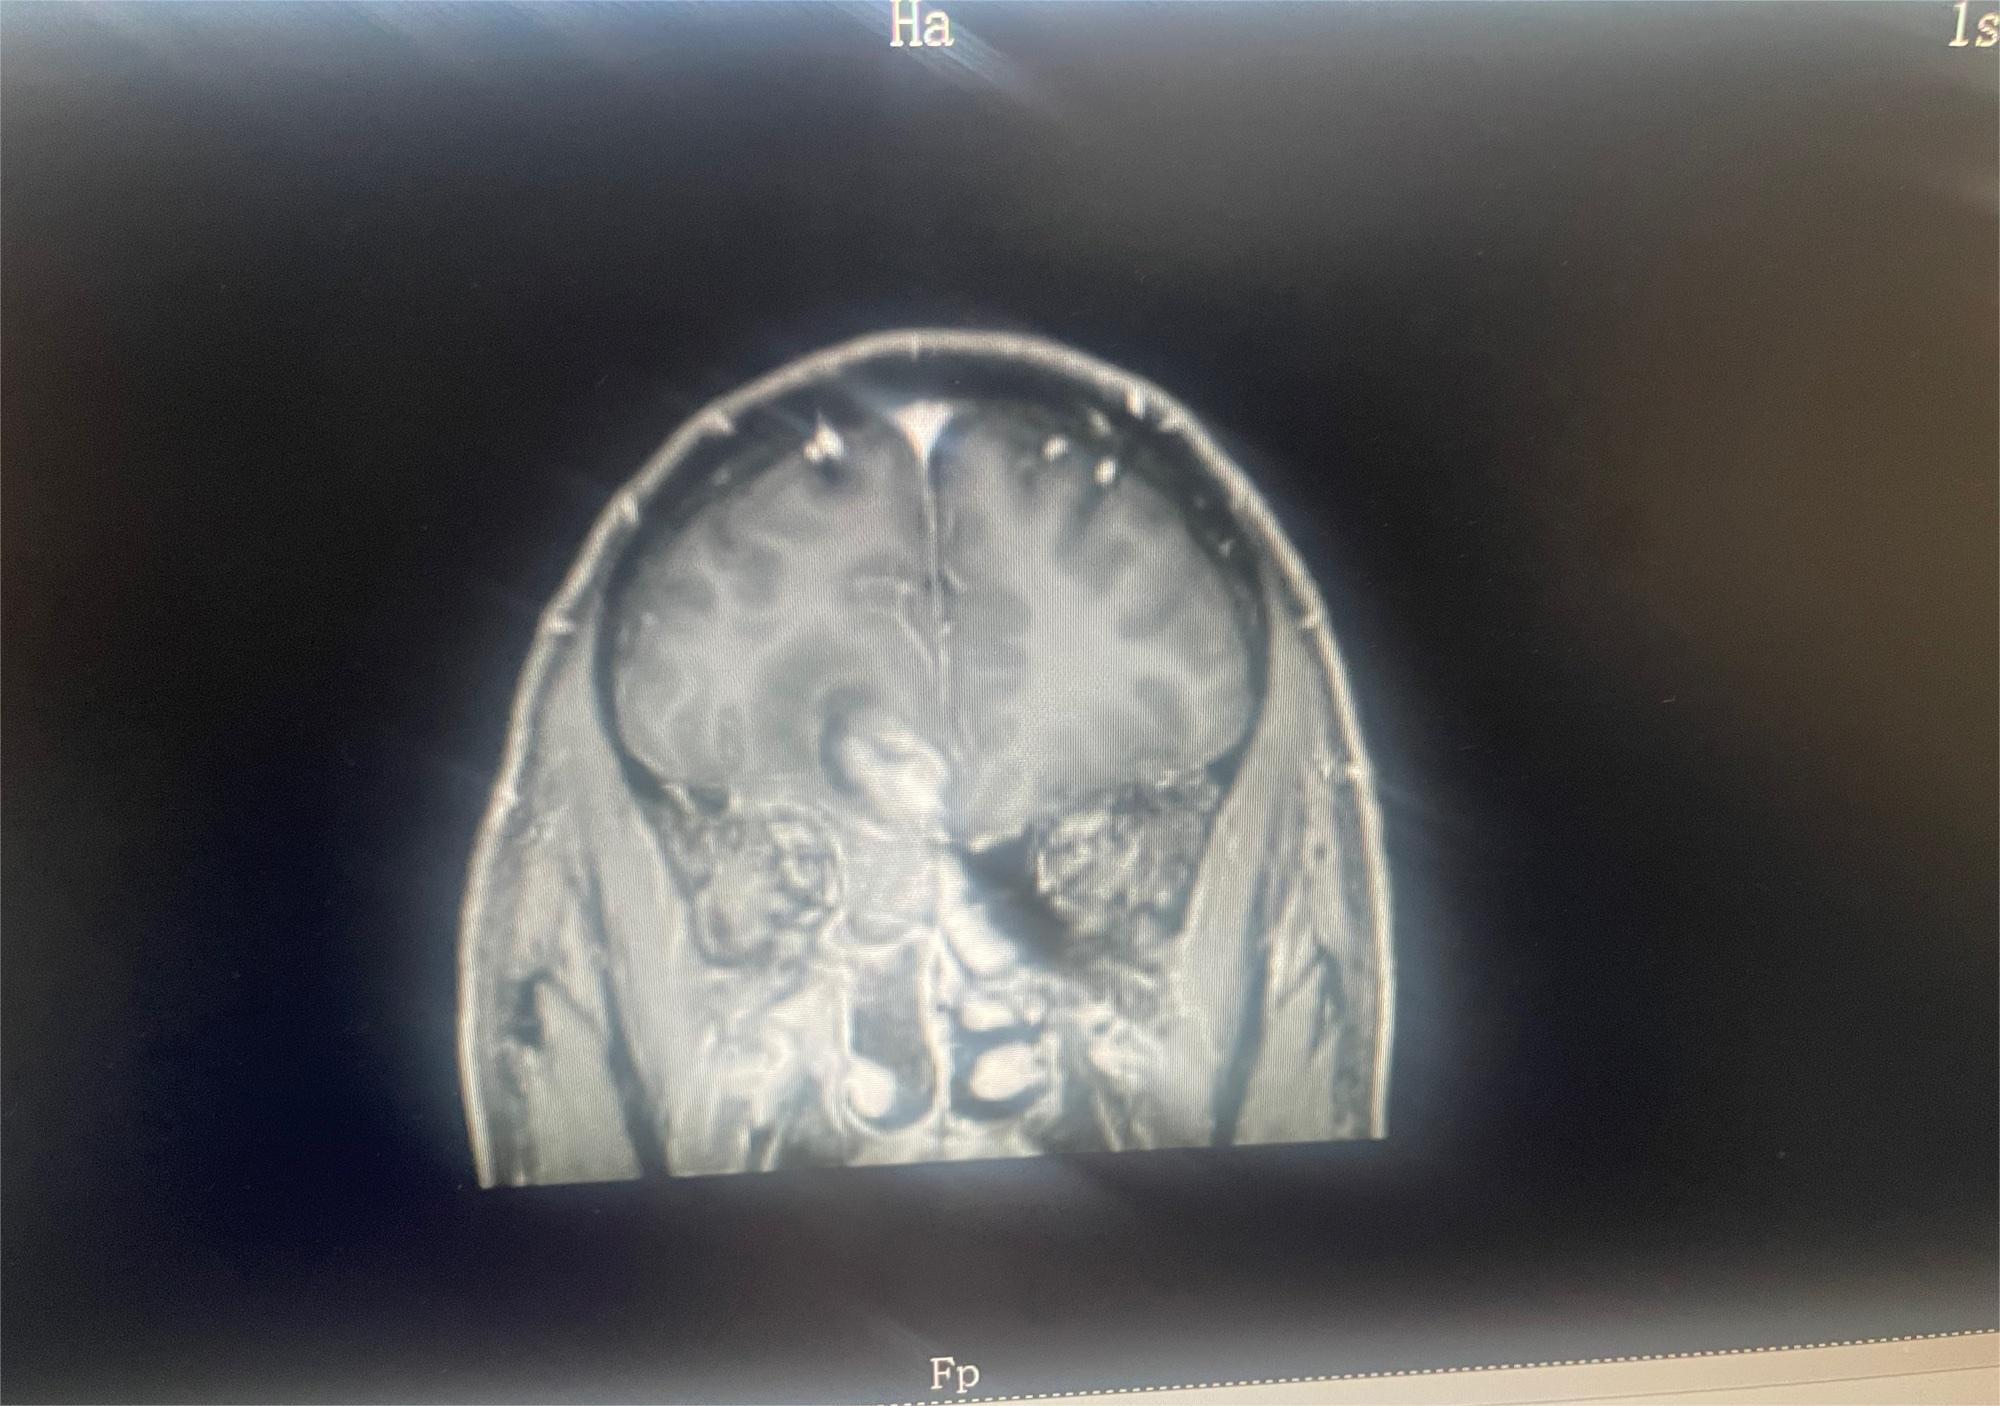

共1张

脑部肿瘤求助